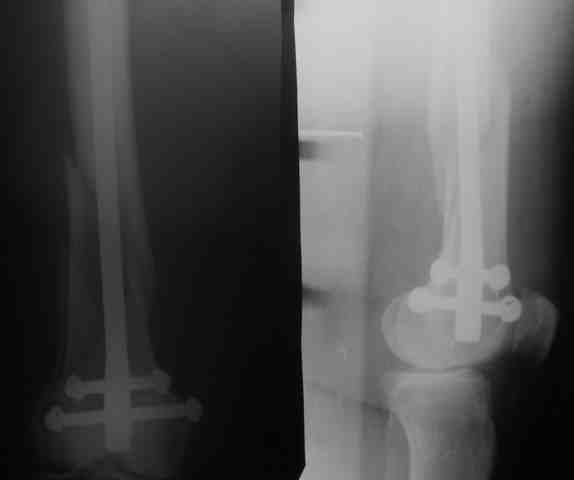

Для ответа на поставленный тобой вопрос важны эти и другие подробности, а догадаться о них сложно, не видно, сколько и какие там отверстия, какие винты диаметром. Лучше сразу писать со всеми этими деталями. Во сколько отверстий попали вверху и внизу винты? Диаметр винтов 5 или 6 мм? Это же определяет ответ на заданный вопрос. Если штифт диаметром 12 и более мм, если он заперт вверху и внизу, и хотя бы по одному винту 6 мм, то безопасна даже немедленная полная нагрузка.

Если винты 5 мм - полная нагрузка не ранее 2 мес. Если винтов вверху нет, да еще и стержень короткий - с нагрузкой еще острожнее.

В верху конец гвоздя не показали. Если винтов в верху нет, на мой взгляд желательно ограничить нагрузку, так как есть риск неправильного сращения из-за того, что может ротироваться отломок на штифте. Да, садиться, разработывать движения в колене, но ходить без нагрузки, до появления рентгенологических признаков образования мозоли.

Если же есть винты (лучше 1 динамический) - то нагрузка не противопоказана

Рг в приложении.

КАН> допущенные ошибки. Спасибо. Рг в приложении.

Снимки вполне симпатичные. Единственное, по ротации не понял, уж больно неразборчивый тот, который без гвоздя.